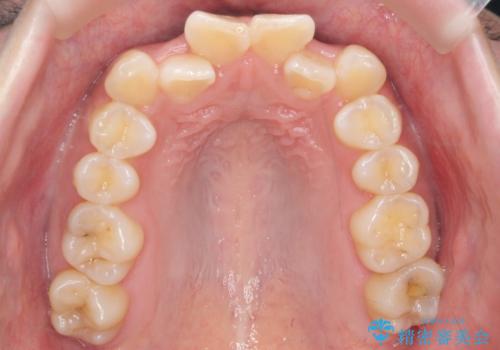

[ 前歯のねじれ・がたつき ] マウスピース矯正

![[ 前歯のねじれ・がたつき ] マウスピース矯正の症例 治療前](https://seimitsushinbi.jp/wp/wp-content/uploads/2024/02/4007c6479f6bce11863dcdd32ed5e39b-500x350.jpg?v=1708502552)

![[ 前歯のねじれ・がたつき ] マウスピース矯正の症例 治療後](https://seimitsushinbi.jp/wp/wp-content/uploads/2024/02/e7a01485e4f4dd0da04705fde4cc34cc-500x350.jpg?v=1708502585)

インビザライン モニター治療 前歯のねじれをまっすぐに